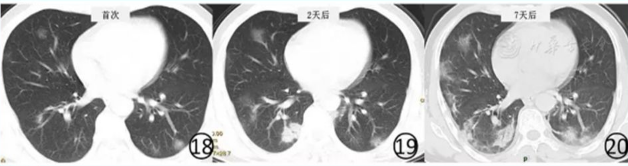

图15 男,38岁。CT平扫肺窗显示右上肺胸膜下有"反晕征" ,肺内有多发的小斑片状磨玻璃阴影, (2)进展期 病变进展时常见有多发新病灶出现。新病灶CT表现与上述早期病灶相似。原有病变多数病灶范围扩大,病灶内出现大小、程度不等的实变(图16,图17),有结节和晕征、实变病灶内可见空气支气管征。原有磨玻璃阴影或实变影也可融合或部分吸收,融合后病变范围和形态常发生变化,不完全沿支气管血管束分布(图18,图19,图20)。

图18~20 男,46岁。基线(图18)CT平扫显示两肺多发淡薄的磨玻璃阴影,左下肺有结节,周围有晕征,病变位于胸膜下。2d后(图19)及7d后(图20)CT平扫显示病变范围不断扩大,出现新病灶,右下肺实变阴影内有支气管充气征 (3)重症期 病变进一步进展,双肺弥漫性实变,密度不均,其内空气支气管征与支气管扩张,非实变区可呈斑片状磨玻璃阴影表现,双肺大部分受累时呈"白肺"表现(图21),叶间胸膜和双侧胸膜常见增厚,并少量胸腔积液,呈游离积液或局部包裹表现。